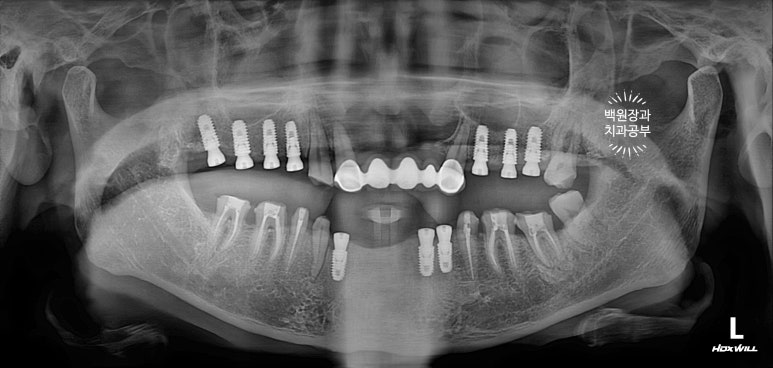

약 3개월 정도 시간이 흘러 위 임플란트의 2차 수술을 시행하였습니다.

위턱뼈에 임플란트를 심은 경우 그 치유기간을 약 3개월 정도로 설정합니다.

건강한 뼈와 새로 위치된 임플란트 사이에 새로운 잇몸뼈 (신생골)가 골유착을 형성하는데 걸리는 시간이지요.

보시면 위 임플란트, 아래 임플란트 모두 뚜껑이 생겨있어요!

임플란트 수술 후 치유기간을 많이들 문의하시는데, 저같은 경우 위턱은 3개월 아래턱은 2개월 기다리고 만약 뼈이식을 하는 경우라면 위치 상관없이 3개월 정도 치유기간을 가집니다.

다만, 요새 저희 치과에서 오스템BA임플란트를 주력으로 사용하면서 치유기간을 2주 정도 줄여보고 있어요!

같은 오스템임플란트라도 SA 인지 CA 인지 BA 인지 확인하고 치료받으시길 권해드립니다.!!

(SA->CA->BA 순으로 출시되었어요.)

임플란트 2차수술 2주가 지나고, 보철 제작을 시작합니다.

임시치아를 먼저 제작해드렸습니다.

시간이 흘러 잇몸이 아물고 위 임플란트의 임시 보철물을 제작해 드렸습니다.

왼쪽은 임플란트에 맞춤형 지대주 (custom abutment)를 연결한 사진이고,

오른쪽은 그 맞춤형 지대주에 임시치아 (temporary crown)을 접착한 사진입니다.

치과용 파노라마 엑스레이를 보시면 더 드라마틱한 변화를 느끼실 수 있어요.

다수의 치아가 씌워지고, 임플란트로 회복되어 마치 사이보그같은(?!) 느낌이 들긴 하지만,

정갈하게 치료가 잘 된 느낌입니다.!!!

임플란트의 위치가 적절히 배치되어 있어, 임플란트에서 크라운까지 이어지는 emergency profile이 예술이네요.

들쭉날쭉한 치아 없이 조화로운 교합이 형성되어 있는 것을 보실 수 있을거에요.

교합평면도 가지런하게 형성되어 보입니다.